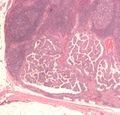

Micrograph of papillary thyroid carcinoma demonstrating prominent papillae with fibrovascular cores. H&E stain.

Micrograph showing that the papillae in papillary thyroid carcinoma are composed of cuboidal cells. H&E stain.

Micrograph (high power view) showing nuclear changes in papillary thyroid carcinoma (PTC), which include groove formation, optical clearing, eosinophilic inclusions and overlapping of nuclei. H&E stain.

Micrograph (high power view) of PTC demonstrating nuclear clearing and overlapping nuclei. H&E stain.

Micrograph of metastatic papillary thyroid carcinoma to a lymph node. H&E stain.

Micrograph of papillary thyroid carcinoma, tall cell variant - high magnification. H&E stain.

Micrograph of papillary thyroid carcinoma, tall cell variant - intermediate magnification. H&E stain.